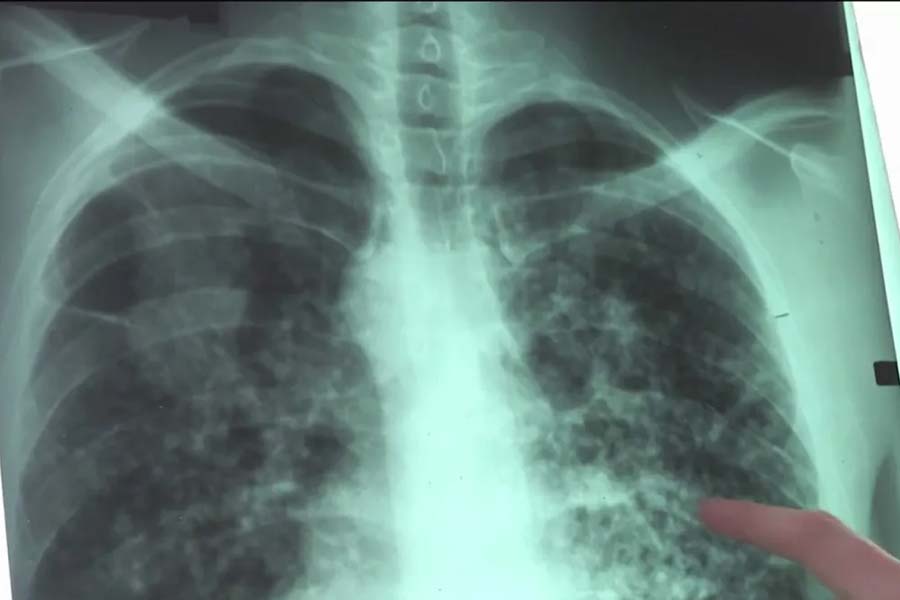

‘হোয়াইট লাং সিনড্রোম’ রোগে সাধারণত ৩ থেকে ৮ বছর বয়সি শিশুরা সংক্রমিত হচ্ছে। আক্রান্ত শিশুদের ফুসফুস পরীক্ষা করে যে ছবি প্রকাশ্যে এসেছে, তা দেখেই রোগটির নাম রাখা হয়েছে।

প্রশাসনের দাবি, সুইডেন এবং ওহায়ো প্রদেশের একাধিক জায়গায় আক্রান্ত শিশুদের হাসপাতালে ভর্তি করানো হচ্ছে। মার্কিন ‘সেন্টার্স ফর ডিজ়িজ় কন্ট্রোল অ্যান্ড প্রিভেনশন’ জানাচ্ছে, তারা নিয়মিত চিনের সঙ্গে যোগাযোগ রাখছে। তবে তাদের বক্তব্য, এই রোগ ফুসফুসের। বুকের এক্স-রে করলেই তা বোঝা যাবে।

আক্রান্ত শিশুদের বুকের এক্স-রে করলে ফুসফুসের উপর সাদা সাদা দাগ লক্ষ করা যাবে। সে কারণেই রোগটির নাম ‘হোয়াইট লাং সিনড্রোম’ দেওয়া হয়েছে।